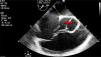

Por severidad del cuadro clínico, inestabilidad hemodinámica y respuesta pobre al manejo se consideró repetir el ecocardiograma, esta vez de forma transesofágica en equipo CX50 portatil, transductor S5-1, por daños valvulares previamente documentados. Éste mostró ventrículo izquierdo de tamaño normal sin disfunción sistólica con solución de continuidad de 9mm en el seno no coronariano, en directa relación con la aurícula derecha por encima de la válvula tricúspide (figs. 1 y 2), gradiente pico de 70mm Hg, válvula mitral e insuficiencia leve, válvula aórtica bivalva e insuficiencia leve, válvula tricúspide engrosada e insuficiencia leve que no permitió calcular la presión sistólica pulmonar, aurícula derecha severamente dilatada (30cm2), dilatación moderada del ventrículo derecho, diámetro basal (45mm) y medio de (39mm), sin disfunción sistólica TAPSE 20mm, pericardio sin colecciones y foramen ovale de 4mm con cortocircuito de izquierda a derecha (fig. 1).